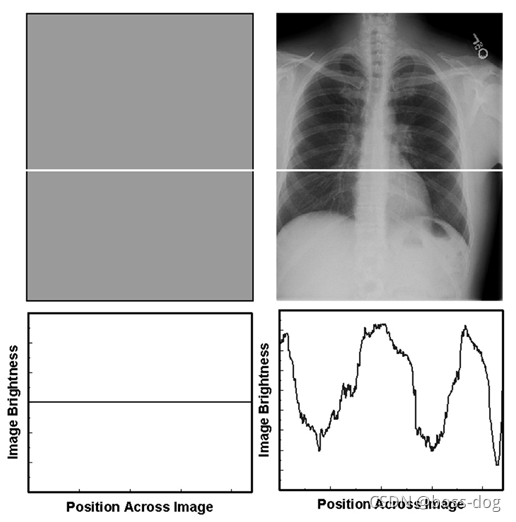

对比度

对比度是指图像上的差异、灰度之间紧密相邻图像上的区域。

对比度的分类:

1)对象本身得对比度

2)探测器(胶片或采集系统)的对比

3)显示成像的对比(给医生看的屏幕对比度怎么样)

X光穿过人体,如骨头吸收的多或者厚的组织吸收的X光多一点,薄的或者如空气、水等吸收X光少一点,则就会出现差别,它们的吸收率(吸收X光的强度)不一样,吸收率公式如下: